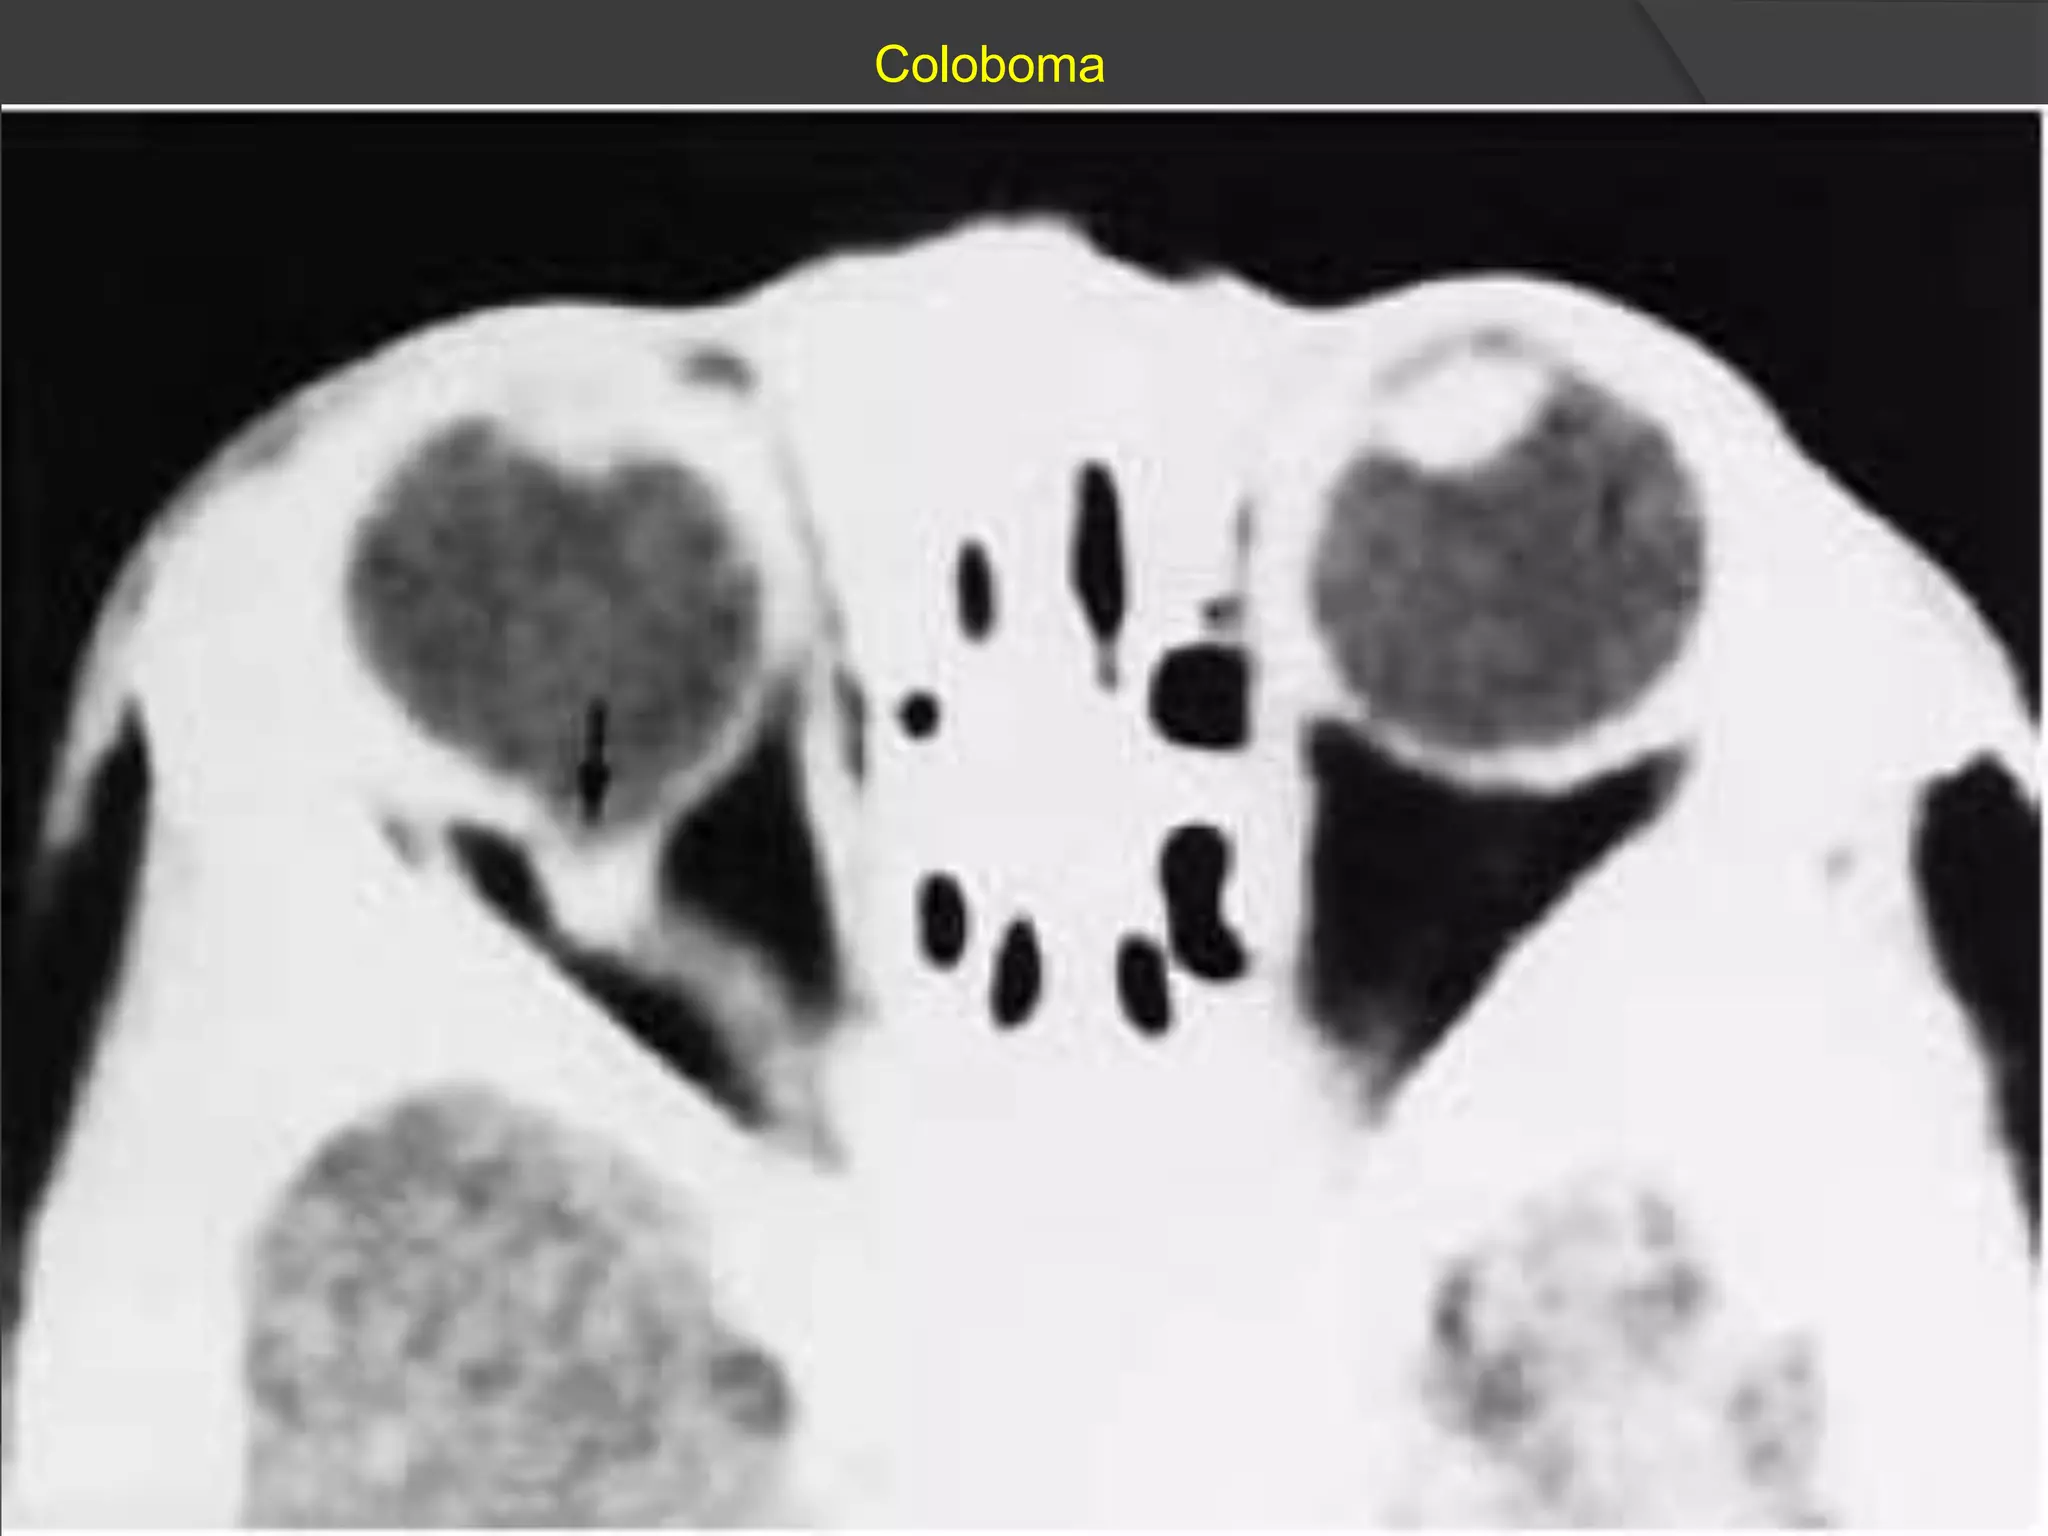

Coloboma

• #7 Typical coloboma of the optic disc. Axial CT scan shows a large posterior global defect (arrow) with optic disc excavation on the right side. The defect appears to be surrounded by an enhancing, deformed sclera and seems to have a direct connection with the vitreous body.